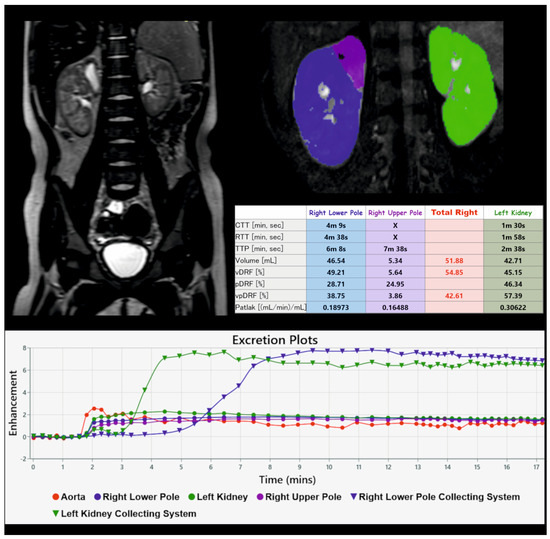

3.2. Magnetic Resonance Urography